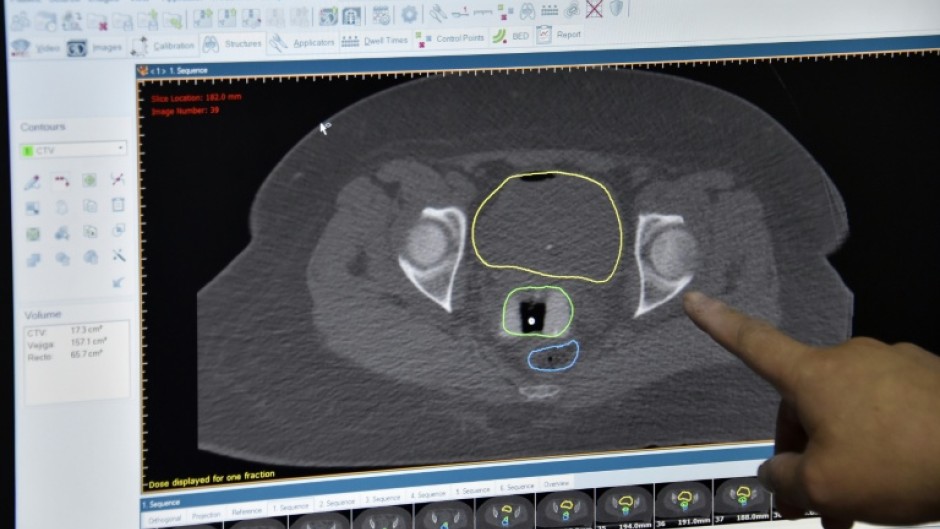

Improvements in cancer survival rates in England and Wales have slowed down significantly since 2010, according to a major study released Wednesday, leading to calls for an urgent national cancer plan.